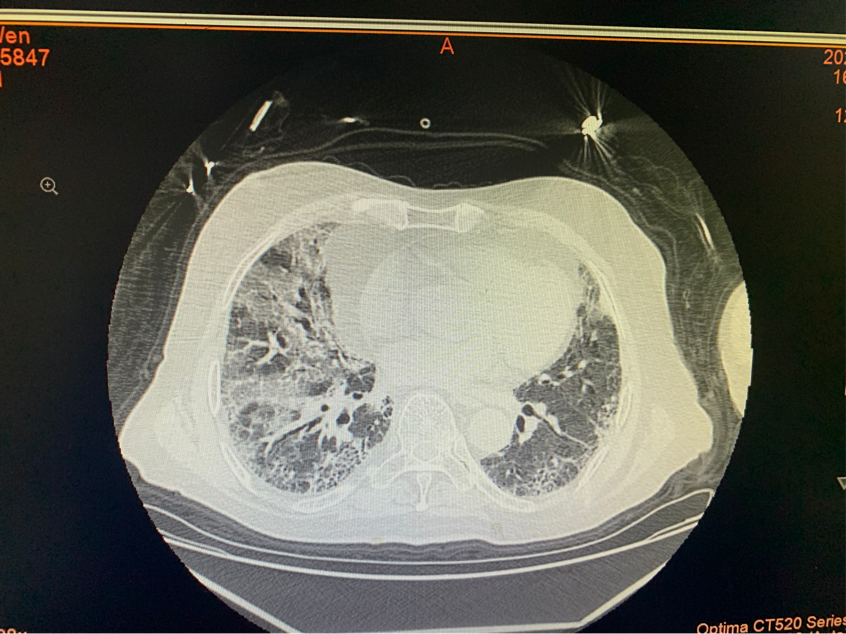

1月5日,一位皮肌炎合并间质性肺炎的女性老年患者因咳嗽、气急、呼吸困难来到风湿结缔组织病科求治。急查CT示重症肺炎,病毒性肺炎,肺纤维化。指脉氧只有78%,立即给予高频呼吸湿化治疗仪,给予激素、抗病毒、巴瑞替尼等药物积极治疗……